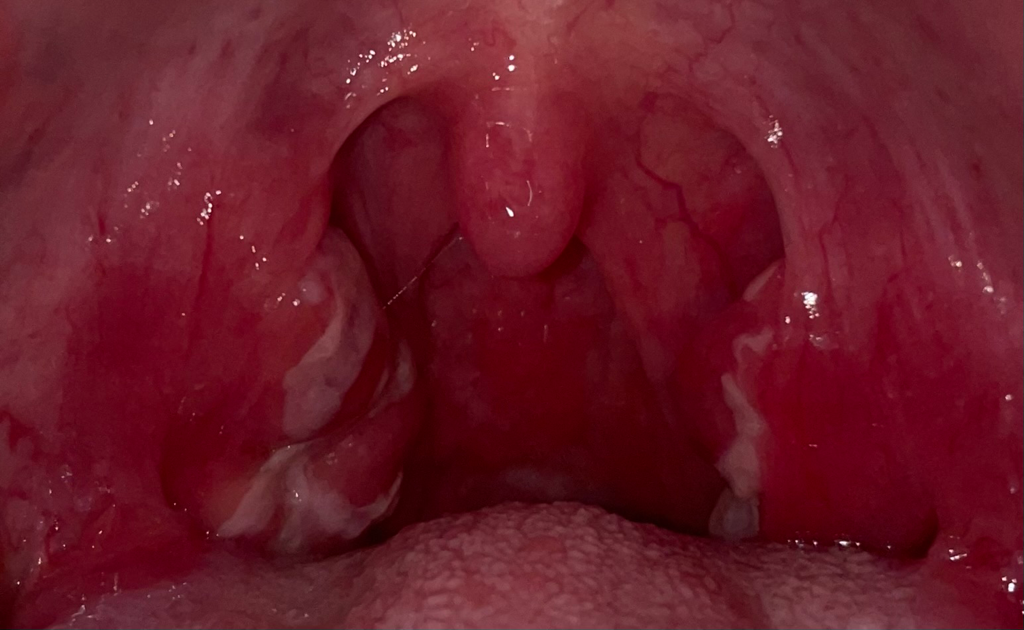

편도염이 생긴거고 대부분은 저절로 호전되지만, 스트렙토코코스 등의 세균에 의하다고 의심되고 증상이 심하면 항생제를 쓰는경우도 있긴합니다.

결국 세균이나 바이러스에 의해 감염으로 염증이 생겼을 가능성이 높아보이긴 합니다.

편도염으로 인한 증상이고, 편도염이 호전되면 사라질 병변이니 너무 걱정하지 않으셔도 괜찮습니다. 약 복용중이시니 이어서 복용해보시고 호전되지 않으면 항생제가 추가되어야 할 수 있으니 병원을 다시 방문해보시기 바랍니다.

인후두 부위의 발적도 심하고 염증이 심한 것 같습니다. 사진에 보이는 하얀색 삼출물은 인후두염에 의하여 발생하고 동반될 수 있는 증상으로 너무 걱정할 것은 없어 보입니다.